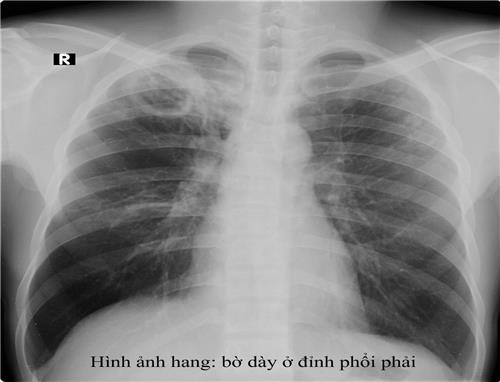

- Xquang phổi thường quy: hình ảnh trên phim X-quang gợi ý lao phổi tiến triển là thâm nhiễm, nốt, hang, có thể 1 bên hoặc 2 bên. Ở người có HIV, hình ảnh X-quang phổi ít thấy hình hang, hay gặp tổn thương tổ chức kẽ và có thể ở vùng thấp của phổi. X-quang phổi có giá trị sàng lọc cao với độ nhạy trên 90% với các trường hợp lao phổi AFB(+). Cần tăng cường sử dụng X-quang phổi tại các cơ sở y tế cho các trường hợp có triệu chứng hô hấp để sàng lọc lao phổi. Tuy nhiên cần lưu ý độ đặc hiệu không cao, nên không khẳng định chẩn đoán lao phổi chỉ bằng 1 phim X-quang phổi. Xquang phổi còn có tác dụng đánh giá đáp ứng với điều trị thử bằng kháng sinh thông thường trước khi chẩn đoán lao phổi không có bằng chứng vi khuẩn và để đánh giá kế quả điều trị lao sau 2 tháng và kết thúc điều trị.

Chẩn đoán xác định: lâm sàng: cấp tính với các triệu chứng ho, sốt cao, khó thở, có thể tím tái. X-quang phổi có nhiều nốt mờ, kích thước đều, đậm độ đều và phân bố khắp 2 phổi (3 đều: kích thước, mật độ và đậm độ cản quang các hạt kê trên phim X-quang phổi). Xét nghiệm đờm thường âm tính. Ngoài ra xét nghiệm vi khuẩn trong các mẫu bệnh phẩm (dịch phế quản, dịch não tủy, máu) có thể dương tính.